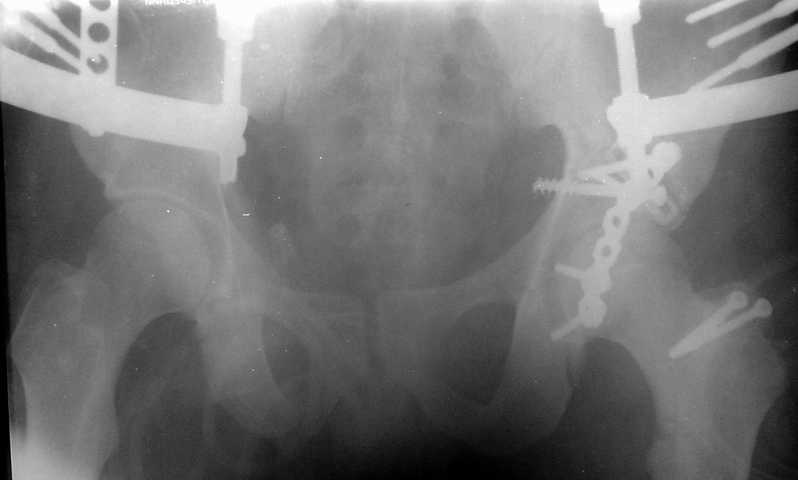

Тяжелая политравма у юноши С. 20 лет - 23.02.20030г. - падение с высоты 8 этажа. В настоящее время состояние стабилизировалось, возможен остеосинтез. Аппарат наложен при поступлении. Д-З: Политравма Перелом С2 б/смещения Перелом левого бедра(см.снимок),правой голени (стабилизирован),обеих пяточных костей со смещением,таза (см.снимок) Нужно ли произвести синтез таза? или ограничиться синтезом бедра? каким??

Оговорюсь сразу, что DHS или DCS не имею, состояние больного позволяет произвести и синтез таза, но надо ли это, учитывая множественность переломов др.локализации? Извиняюсь, что нет др. снимков и за качество, сканер с незким разрешением. Благодарю за советы !

Пока видно, что имеется тяжелый оскольчатый перелом вертлужной впадины, который надо открыто синтезировать. Для уточнения диагноза необходимо сделать косые проекции (Judet views). Не помешала бы КТ.

Травма 17 ноября 2002 г., поступил к нам 1 декабря, оперирован 8-го - открытая репозиция, остеосинтез пластинками и винтами. Учитывая повреждение переднего полукольца справа, и крестца и крестцово-подвздошного сочленения слева, наложили аппарат на 2 месяца.

Для экономии места привожу интра- и послеоперационный обзорный снимок, без дополнительных проекций.